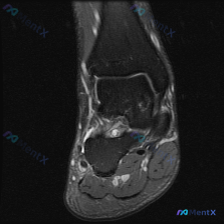

这是一例踝关节MRI冠状位T2加权像,我们先做系统性解剖评估:

- 骨与关节:胫距关节、距下关节间隙正常,关节面平滑,胫骨远端、距骨、跟骨骨髓信号均匀,没有骨赘、软骨下囊肿、骨折线或异常骨髓水肿

- 韧带结构:内侧三角韧带走行连续,信号正常;外侧韧带因切面观察受限,但周围没有明显软组织积液水肿

- 肌腱结构:内踝后方踝管区的胫后肌腱、趾长屈肌腱、踇长屈肌腱,以及外踝后方的腓骨肌腱,形态信号都正常

- 关键异常发现:距骨与跟骨之间的跗骨窦区域,可见局限性T2高信号影,内部信号略杂乱,周围伴随轻度软组织水肿

看到异常信号先定位置,这个高信号不是弥漫性软组织水肿,正好位于跗骨窦这个特殊解剖结构里——跗骨窦是距骨跟骨之间的漏斗状间隙,里面本来是脂肪,还有韧带、血管、神经,所以问题肯定出在这里,不是泛泛的软组织积液。

结合「优先考虑常见病」的原则,这个病例的异常信号非常局限,正好位于跗骨窦,其余结构都正常,所以最可能的诊断就是跗骨窦综合征(跗骨窦区域炎性改变伴积液)。